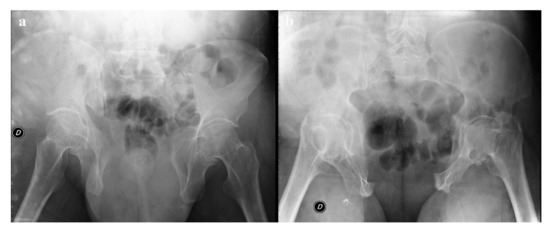

Review

Imaging Review of Pelvic Ring Fractures and Its Complications in High-Energy Trauma

by Edoardo Leone, Andrea Garipoli, Umberto Ripani, Riccardo Maria Lanzetti, Marco Spoliti, Domenico Creta, Carolina Giannace, Antonio Galluzzo, Margherita Trinci and Michele Galluzzo

Pelvic ring fractures are common in high-energy blunt trauma, especially in traffic accidents. These types of injuries have a high rate of morbidity and mortality, due to the common instability of the fractures, and the associated intrapelvic vascular and visceral complications. Computed tomography [...] Read more.

Pelvic ring fractures are common in high-energy blunt trauma, especially in traffic accidents. These types of injuries have a high rate of morbidity and mortality, due to the common instability of the fractures, and the associated intrapelvic vascular and visceral complications. Computed tomography (CT) is the gold standard technique in the evaluation of pelvic trauma because it can quickly and accurately identify pelvic ring fractures, intrapelvic active bleeding, and lesions of other body systems. To properly guide the multidisciplinary management of the polytrauma patient, a classification criterion is mandatory. In this review, we decided to focus on the Young and Burgess classification, because it combines the mechanism and the stability of the fractures, helping to accurately identify injuries and related complications. Full article